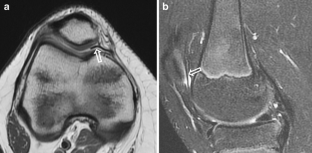

Fig. 3